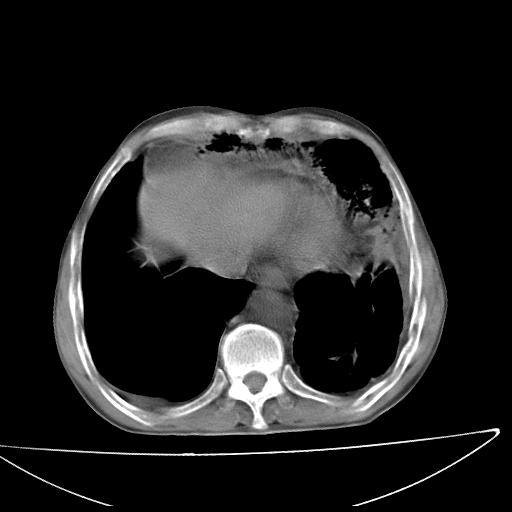

男  70岁,发烧咳嗽4天。盗汗,消瘦。无痰中带血丝,以前有肺tb病史,ct见,双肺tb,左侧胸廓塌陷,左胸膜肥厚粘连。纵隔移位,右侧胸腔积液,大家说说那个心影前左肺舌叶除了肺大炮还有炎症还是干酪性肺炎?有占位吗?我看纵隔淋巴结也大。

1)两肺继发性肺结核并左肺上叶肺不张,支气管扩张。2)双侧胸膜炎(胸膜增厚+少量胸腔积液)。

两肺继发性肺结核并感染,左肺上叶肺不张。建议ct增强。